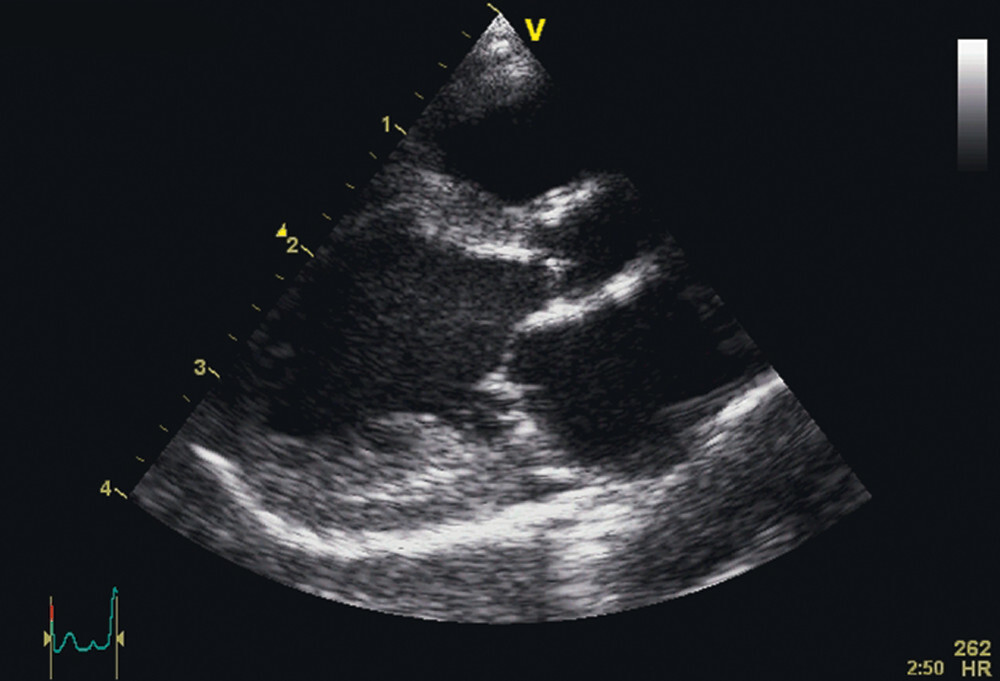

Die Echokardiografie ist notwendig, um die definitive Diagnose DCM stellen zu können. Hier fällt eine linksventrikuläre und linksatriale oder generalisierte Volumenüberladung auf (Abb. 1), zudem liegt eine deutliche systolische Dysfunktion vor. Enddiastolischer und endsystolischer linksventrikulärer Kammerdurchmesser sind vergrößert. Das linke Atrium ist je nach Schweregrad der Erkrankung mehr oder weniger stark dilatiert. In der Farbdopplerechokardiografie können sekundäre, durch die Volumenüberladung und die Dilatation des Atrioventrikularklappenannulus bedingte Mitral- und Trikuspidalklappeninsuffizienzen gefunden werden [39][42].